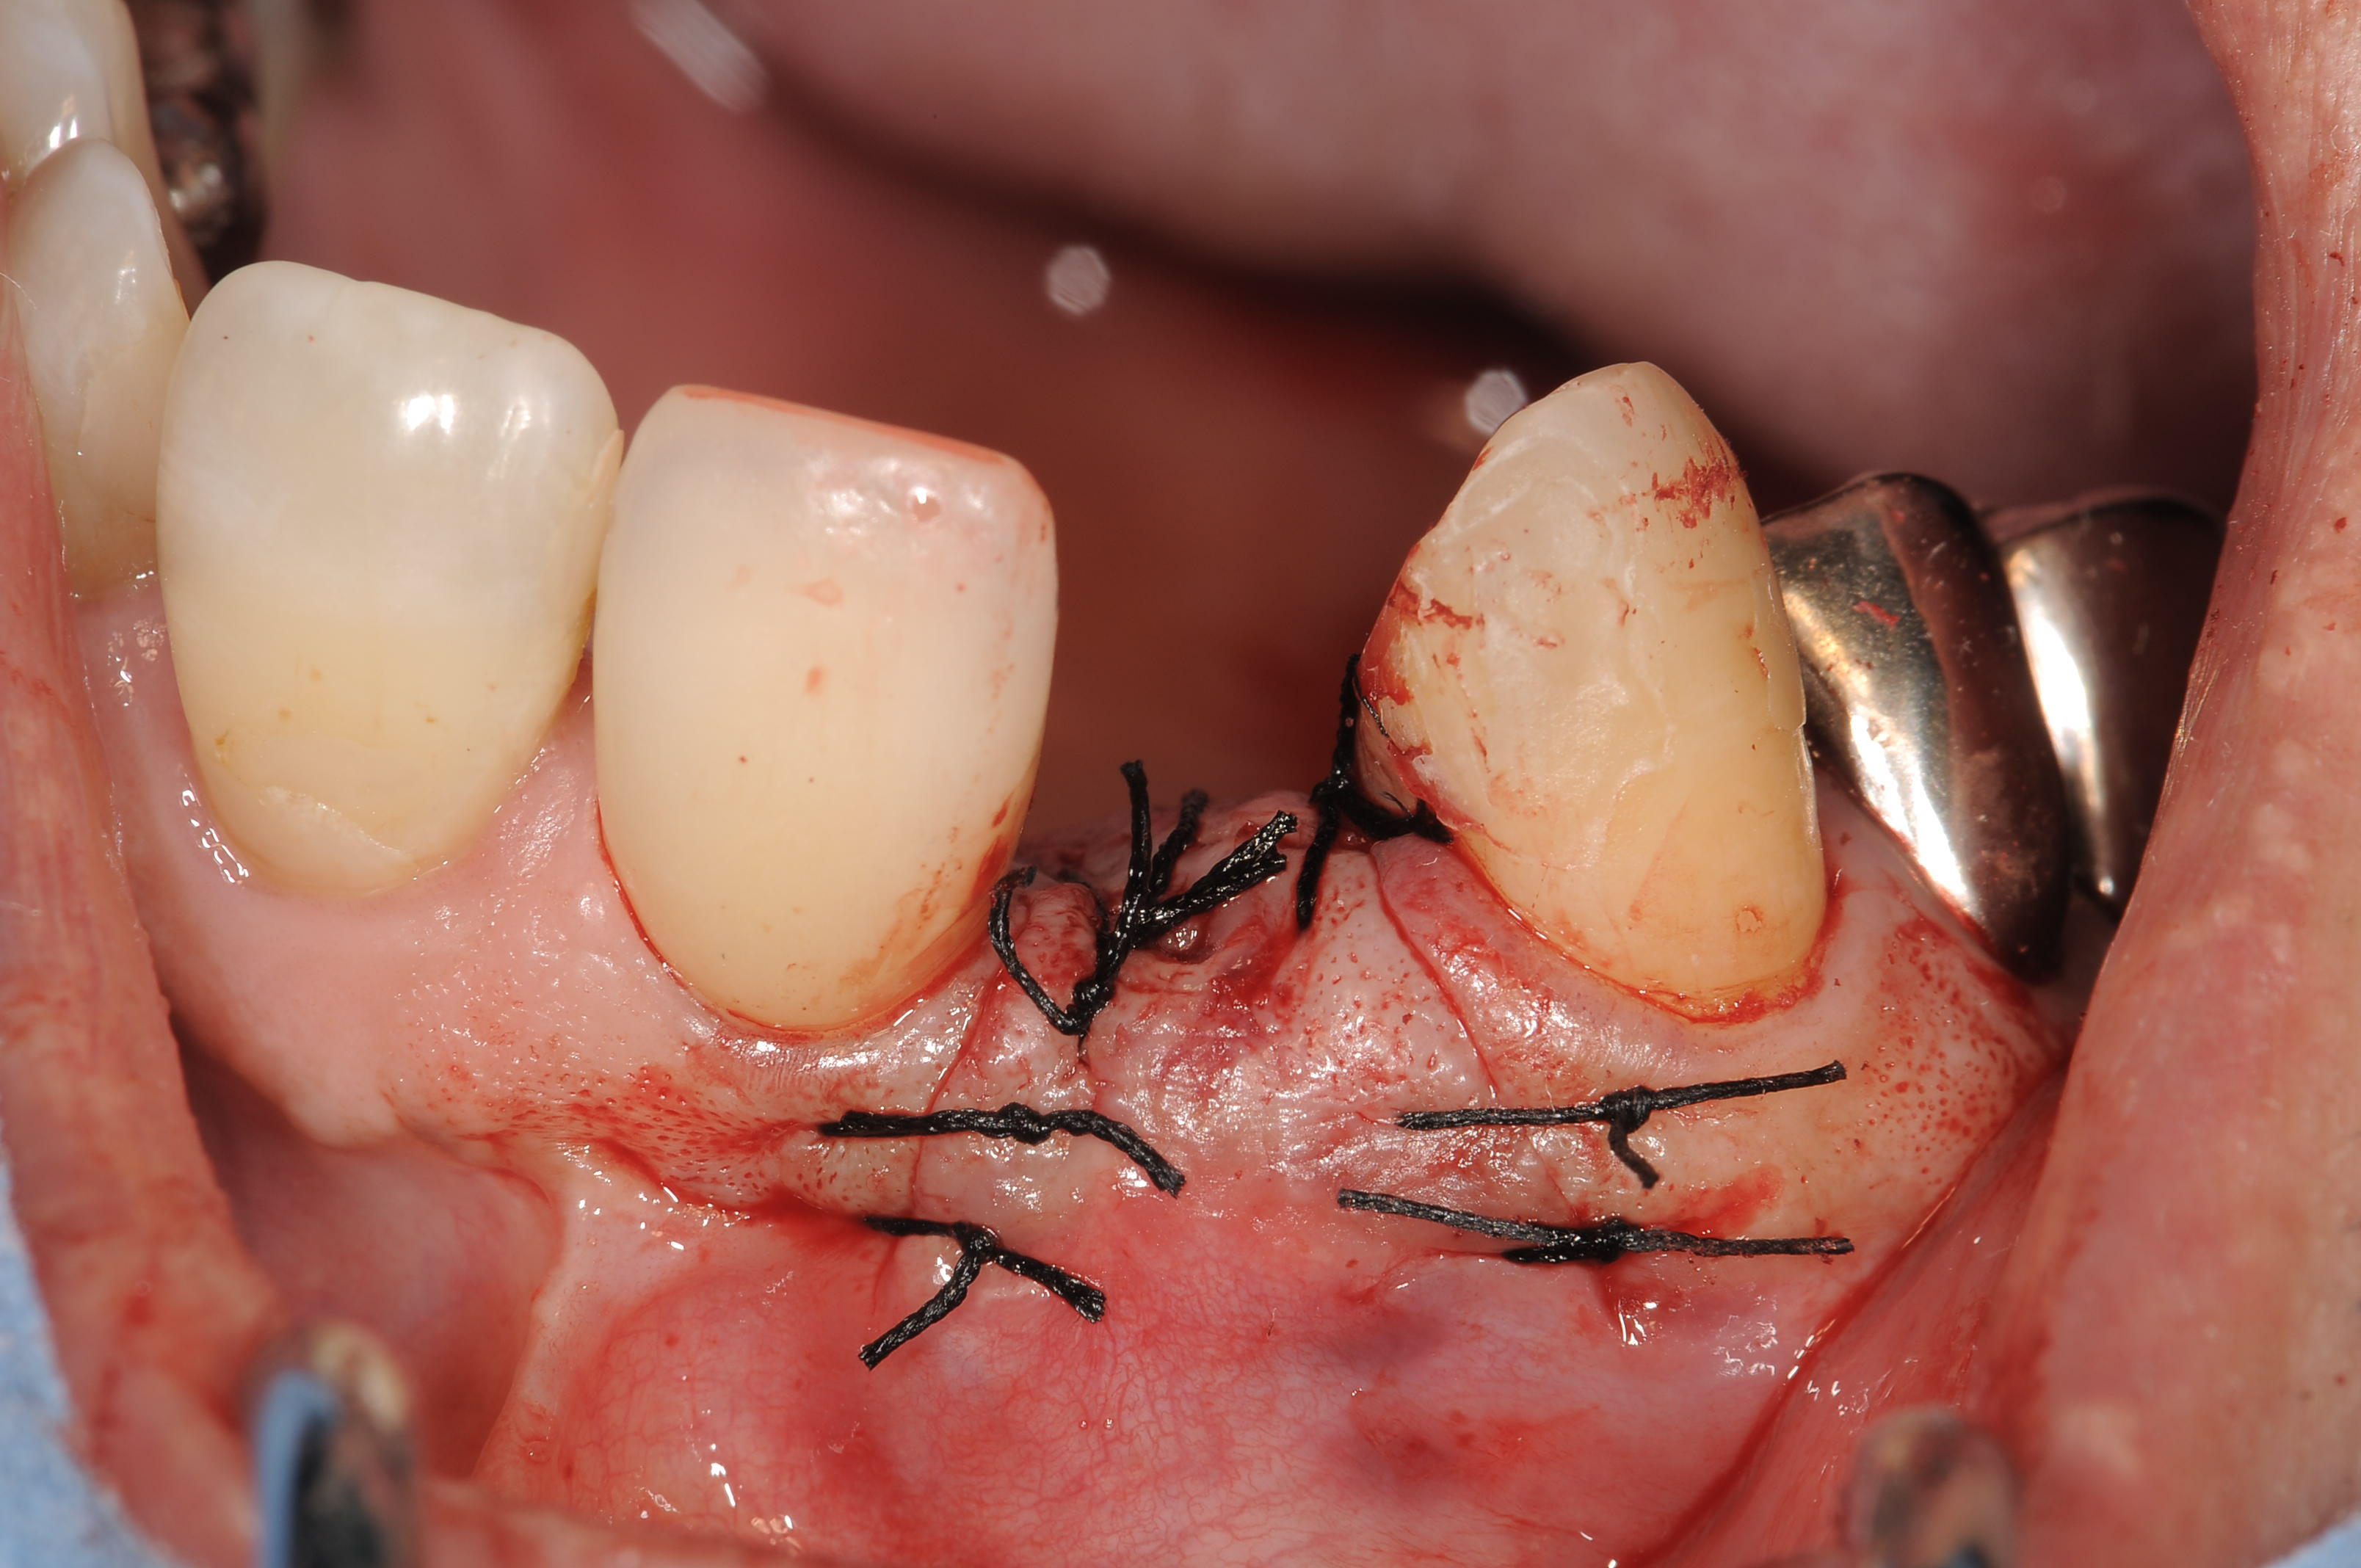

リミテットフラップデザインにて完全埋入しています。